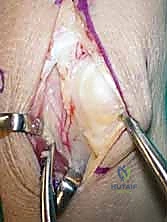

3. الجزء الحاسم: لا يتم أخذ العظم فحسب، بل يتم استئصاله مع الشريان والوريد المتصلين به (Pedicled graft). هذا يعني أن قطعة العظم المنقولة لا تزال حية وتنبض بالدم.

5. يُزرع الطعم العظمي الحي (الوعائي) داخل التجويف الذي تم إنشاؤه في العظم الهلالي.

6. تعمل الأوعية الدموية المنقولة كـ "شريان حياة" جديد، حيث تبدأ في تغذية العظم الهلالي، مما يحفز الخلايا العظمية (Osteoblasts) على بناء نسيج عظمي جديد وقوي.

لماذا الدمج بين الإجراءين هو الحل الأمثل؟

الجمع بين تطويل (أو زراعة) العظم الوعائي وتقصير العظم الكبير يُعد ضربة مزدوجة لمرض كينبوك. الطعم الوعائي يعالج المشكلة البيولوجية (نقص الدم)، وتقصير العظم الكبير يعالج المشكلة الميكانيكية (الضغط المفرط). أثبتت الدراسات الطبية الحديثة أن هذا النهج المزدوج يوفر أعلى معدلات النجاح في الحفاظ على شكل العظم الهلالي، تخفيف الألم، ومنع تطور خشونة الرسغ.